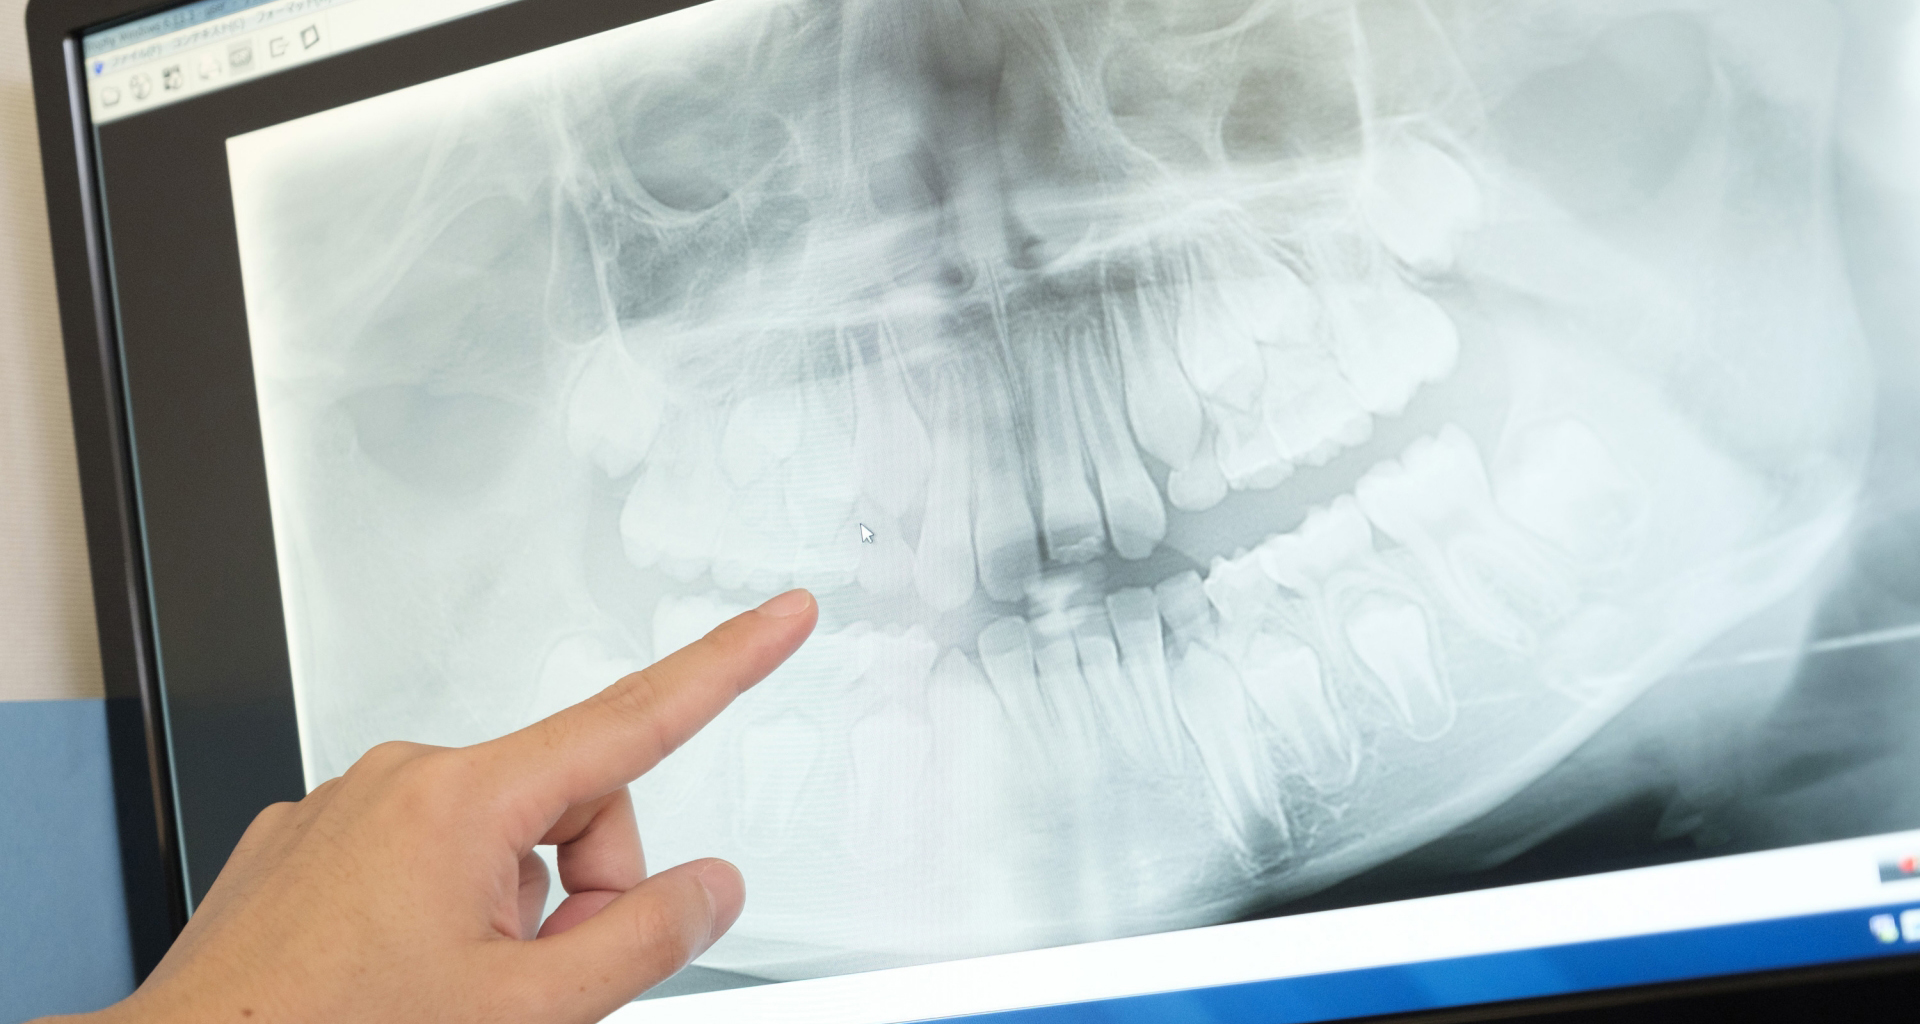

レントゲン写真(治療前)

担当医師所見

根の治療を3本すでに治療されています。1本根の奥の詰め物が疎になっていますので、根の部分の再治療も行う必要がありそうです。銀歯の中で虫歯になっているものもあります。